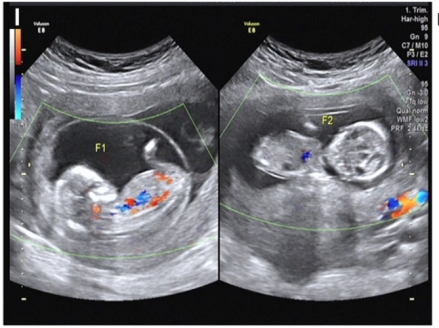

图:46,XX/46,XY嵌合体女性通过辅助生殖技术成功妊娠双胎的影像学图,双胎卵子均为X,其中一个卵子的颗粒细胞100%均为XY核型,一个卵子的颗粒细胞为46,XX/46,XY嵌合体核型